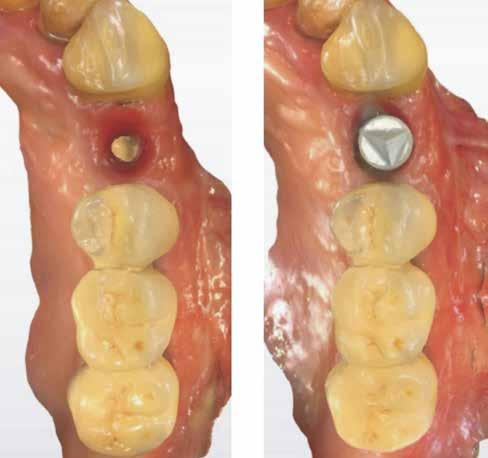

bukkális 1. kép: Kiindulási állapot, 2020. január. 3. kép: Kiindulási CBCT felvétel. 2. kép: Kiindulási állapot a palatinális oldal felől.

A részleges extrakció befejezése után következhet az implantátumágy preparálása a gyártó utasításai szerint (6.

kép). A bemutatott esetben Nobel Replace CC 4,3x13mm implantátumot helyeztünk be, amely a bukkális oldalon direkt kontaktusba került a megmaradt foggyökérdarabbal (7. kép). Az alveolus oldalfalai és a körszimmetrikius implantátum közötti hézag kitöltésére bovin eredetű xenograftot (Creos S xenogain) használtunk (8. kép). A hasonló

5. a–e képek: Részleges extrakció. 4. a–c képek: A fog dekoronálása.

6. kép: Implantátum-ágy preparáció. 7. a–b. képek: Implantátum behelyezés. 8. kép: A behelyezett implantátum. 10. a–b képek: Azonnali ideiglenes korona készítése. 9. kép: Megfelelő primer stabilitás.